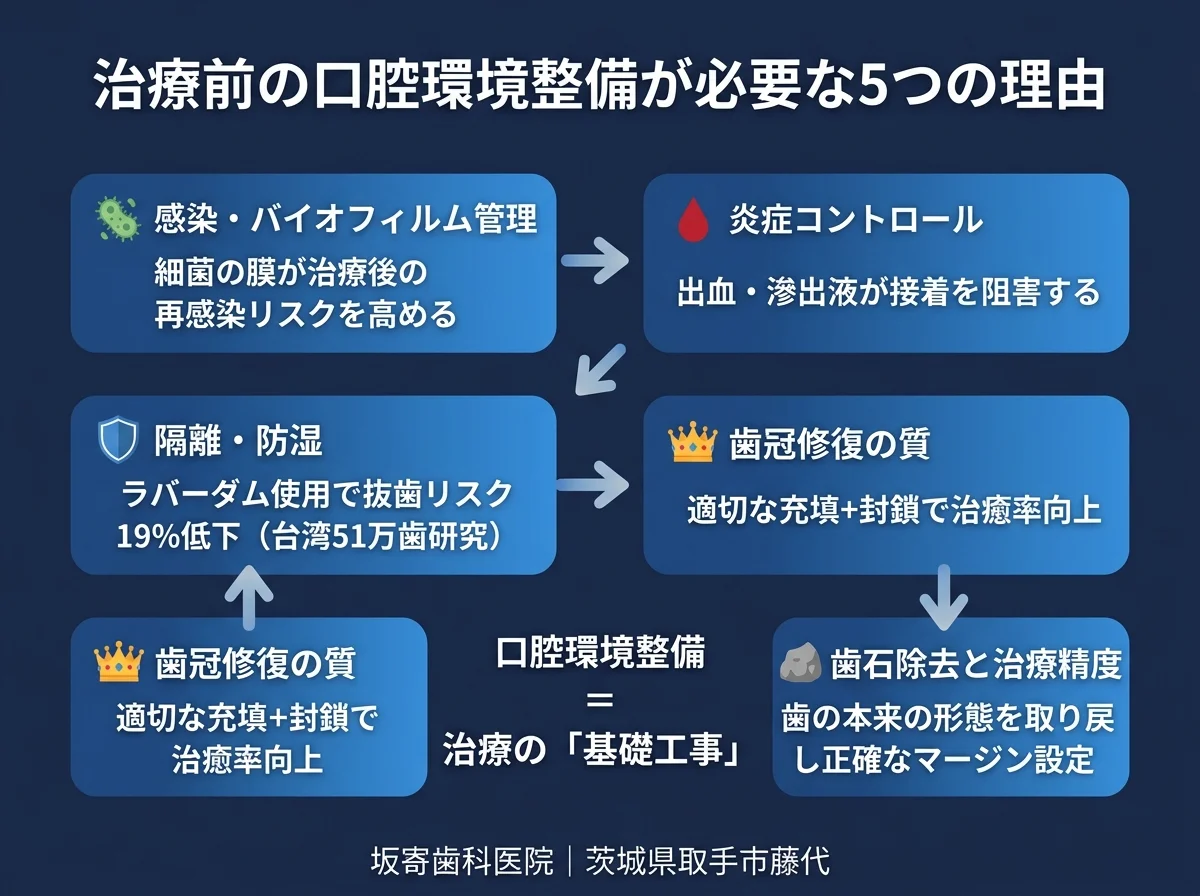

治療前のクリーニングは"金儲け"?

「治療前のクリーニングは金儲けでは?」という疑問に、根管治療・コンポジットレジン修復の予後に関する科学的根拠から歯科医師が正直にお答えします。